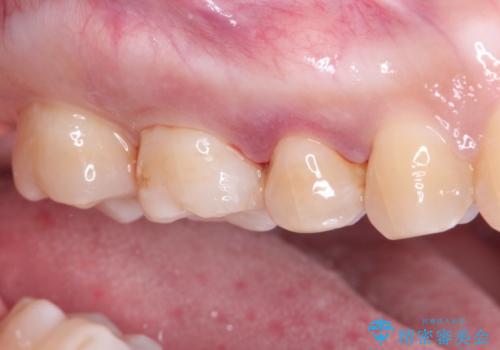

- 虫歯の治療を主訴に来院されました。メタルフリーによる治療を希望されましたので、セラミックインレーにて修復治療を行っております。

当院でのセラミックインレーはすべてe-maxと呼ばれる高強度セラミックにて製作されます。

また、製作方法もプレスと呼ばれる方法を用いることで精度を高めています。